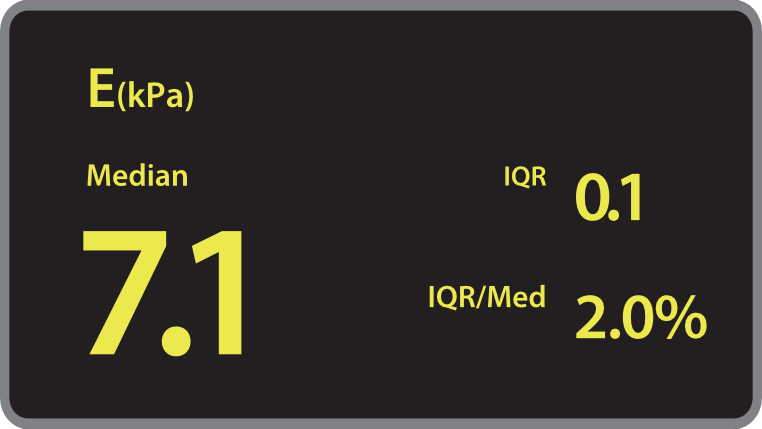

O Hepatus ÃĐ um equipamento de diagnÃģstico profissional n?o invasivo para doen?as hepÃĄticas que fornece resultados quantitativos que indicam o estÃĄgio da fibrose hepÃĄtica. Ele ÃĐ preciso, eficiente, confiÃĄvel e adequado ao acompanhamento de doen?as, abrindo uma nova era para o diagnÃģstico n?o invasivo de doen?as hepÃĄticas.

? aplicÃĄvel à triagem, ao diagnÃģstico, ao monitoramento e à avalia??o do tratamento da fibrose e da esteatose hepÃĄticas devido a vÃĄrios motivos. Especialmente durante o estÃĄgio inicial.